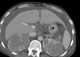

Bilateral renal infarction